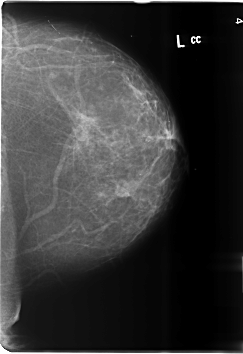

B_3486_1.LEFT_MLO

B_3486_1.LEFT_CC

LEFT_MLO LINES 6000 PIXELS_PER_LINE 4184 BITS_PER_PIXEL 12 RESOLUTION 50 NON_OVERLAY

LEFT_CC LINES 6016 PIXELS_PER_LINE 4128 BITS_PER_PIXEL 12 RESOLUTION 50 NON_OVERLAY